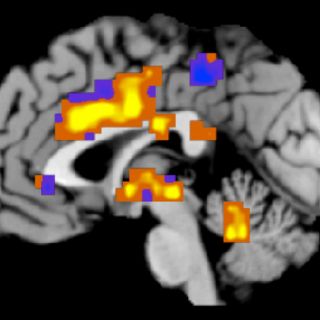

El estudio lo llevaron a cabo científicos del Instituto neurológico de Montreal (Canadá), y la Universitad de Utrecht (Holanda), entre otros, empleando la imagen funcional por resonancia magnética que capta figuras del cerebro durante la actividad.

Otros estudios ya han demostrado que el escuchar música afecta e involucra no sólo la corteza auditoria del cerebro sino también las regiones de las emociones y los circuitos mesolímbicos vinculados con la gratificación. Hay estudios que han demostrado que la dopamina interviene en esta respuesta en las áreas estriadas del cerebro.